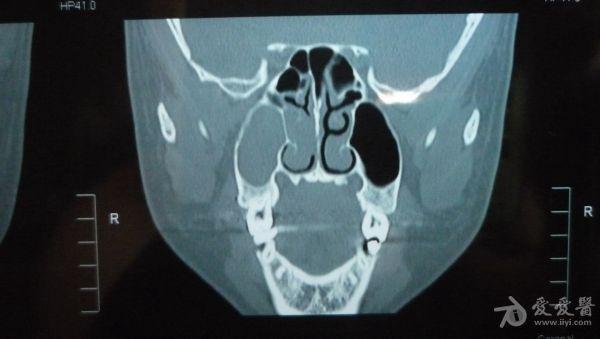

CT结果是右侧上颌窦及部分筛窦窦腔内见稍高密度影填充,CT值约21U,窦壁骨质未见破坏征象;鼻腔后部亦见少量稍高密度影填充;左侧上颌窦、筛窦及蝶窦、额窦未见明显异常。CT图片见附件。医生说我的右边鼻窦都被软组织堵死了,必须要做手术清楚后再做病理分析看是良性还是恶性。

想请问下医生:CT图片上右边的上颌窦内的稍高密度影,是软组织还是液体的几率大些呢